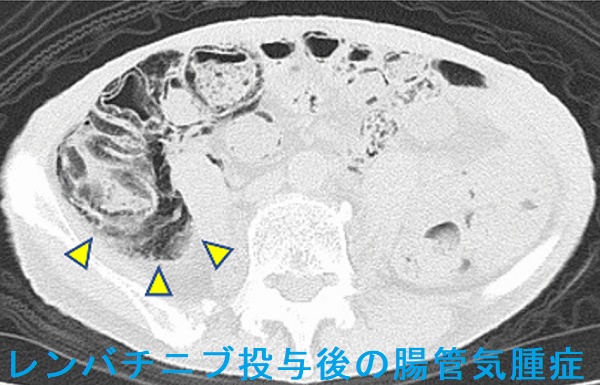

腸管気腫症(pneumatosis intestinalis)とは、大腸壁や小腸壁の粘膜下層・漿膜下層にガスが溜まり、気腫(空気嚢胞)を形成する病態。原因として、約15%は特発性ですが、約85%は続発性で、

分子標的薬(チロシンキナーゼ阻害薬) ベバシズマブ(アバスチン®)[甲状腺機能低下症も併発]、スニチニブ、レンバチニブ[J Med Case Rep. 2021 Nov 12;15(1):556.]、ダブラフェニブ・トラメチニブ[J Med Case Rep. 2021 Mar 2;15(1):109.];腸壁への血流障害

腸管気腫症は、無症状で自然軽快することが多い。腹痛・血便を伴う場合は絶食や酸素投与、手術切除。